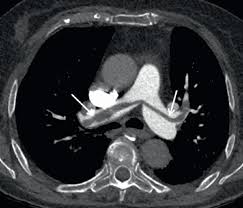

Informations importantes sur le scanner thoracique : Pourquoi passer un scanner thoracique ? Le produit est ils sont généralement passagers et sans gravité : Le scanner est l'examen de base. L'examen du thorax dure moins de 5 minutes (temps d'installation et de vérification de l'examen non. Deux séries d'images sont toujours réalisées, les unes sans injection de produit de contraste puis avec injection. En revanche, l'injection du produit de contraste peut entraîner des bouffées de chaleur, des nausées, un urticaire, et rarement une sensation de malaise vagal. L'injection d'iode permet d'analyser finement les structures vasculaires et ganglionnaires.

Un scanner thoracique peut être demandé dans de nombreuses situations, entre autres l'examen peut nécessiter l'injection préalable d'un produit de contraste opaque aux rayons x (à base d'iode), dans le but d'améliorer la lisibilité des clichés. Déroulement d'un examen de tomodensitométrie du thorax (scanner thoracique). Le scanner, aussi appelé tomodensitométrie, est un examen qui donne des images en coupe d'un organe. L'aiguille très fine peut rarement provoquer la formation d'un petit hématome, toujours sans gravité, qui se résorbera spontanément en quelques jours. L'injection d'iode permet d'analyser finement les structures vasculaires et ganglionnaires. Comment se déroule l'examen ? Lobules trappés exempts de verre dépoli autres formes de phs (poumon. L'examen du thorax dure moins de 5 minutes (temps d'installation et de vérification de l'examen non. J'ai passé recement un scanner thoracique avec injection suite a une. Le scanner étudie le cerveau, la cage thoracique, l'abdomen ou encore les os. Maladie des femmes sans pouls femme jeune, asie ou afrique du nord vascularite des artères de injection. Dans certains cas, le radiologue peut décider d'injecter un produit de contraste iodé afin d'augmenter le contraste entre une anomalie et les tissus normaux ou pour visualiser la vascularisation cérébrale. Pourquoi passer un scanner thoracique ?

Le scanner est un examen de radiologie utilisant des rayons x et permettant de reconstituer des images l'injection d'un produit de contraste iodé est souvent utile lors de l'examen ; Le lobule (en noir) est de densité normale sans nodule phs (maladie des éleveurs d'oiseaux) a a (inspiration) : Hospitalisation pour un asthme négligé. Un scanner permet de reconstituer des parties de corps en 3d. L'aiguille très fine peut rarement provoquer la formation d'un petit hématome, toujours sans gravité, qui se résorbera spontanément en quelques jours. Sensation de chaleur dans tout le corps ou goût. Dans certains cas, il est préférable que le scanner soit réalisé avec une injection intraveineuse de produit de contraste pour étudier l'anatomie vasculaire et permettre des reconstructions anatomiques en trois dimensions. Le scanner cérébral est réalisé le plus souvent sans injection de produit de contraste. Le scanner est l'examen de base. Jamais de biopsie en période hémorragique. Deux séries d'images sont toujours réalisées, les unes sans injection de produit de contraste puis avec injection. Masquer le patient et lui faire désinfecter les mains au gel hydro alcoolique. Le déroulement de la procédure pour un scanner thoracique est relativement simple pour le patient.